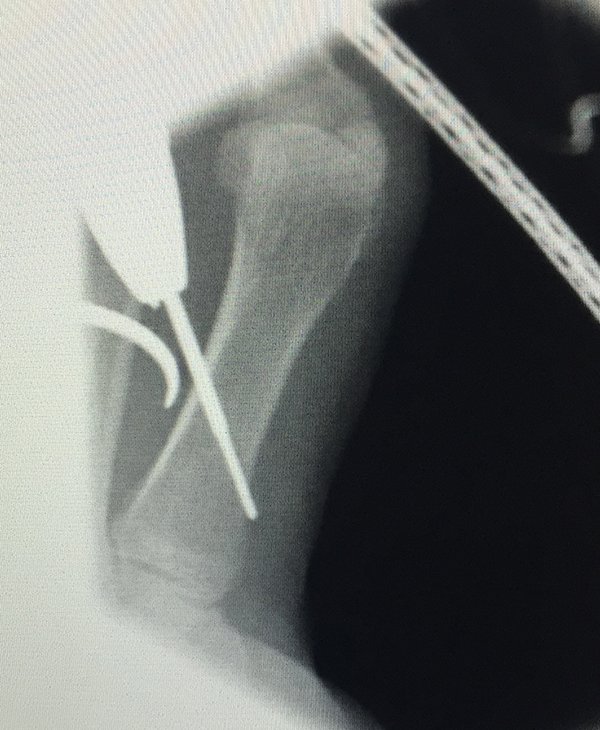

Zusätzlich schränken Wachstumsfugen die Wahl der Osteosynthese ein. Eine die Fuge kreuzende Osteosynthese ist ausschließlich mit Kirschner-Drähten möglich (Abb. 3).

Abb. 3 a-j: Beispiel einer Calcaneusverschiebeosteotomie mit offenen Wachstumsfugen und der entsprechenden Osteosynthese mit Kirschner Drähten. Lokalisation der Osteotomie (a), Lage der Fräse (b-d), Drahtlage mehrere Ansichten (e-h), Heilung der Osteotomie 4 Wochen postoperativ und Entfernung der Drähte (i-j).

Zum Lesen der Bildbeschreibung und zur Vollansicht bitte die Bilder anklicken. Bilder: A. Helmers.